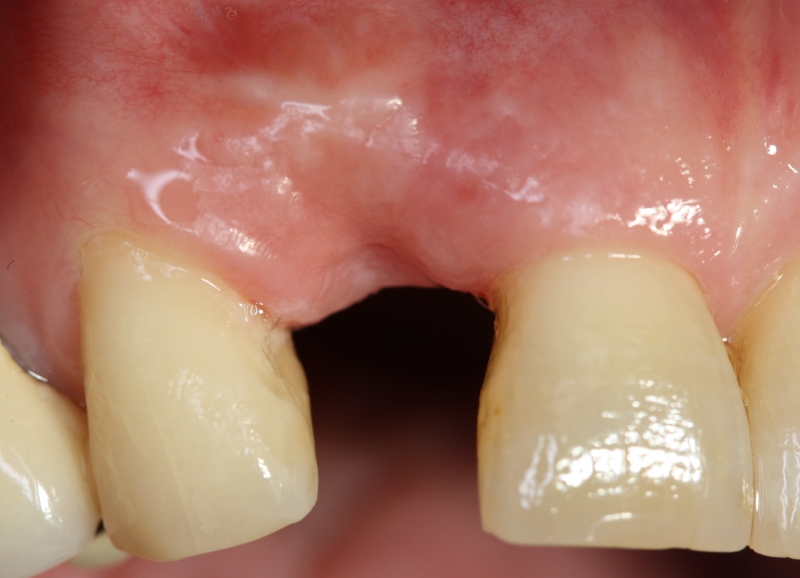

07/20 - Second surgical site: clinical situation preoperativelyGBR with maxresorb® & Jason® membrane - Prof. Dr. Dr. D. Rothamel

-